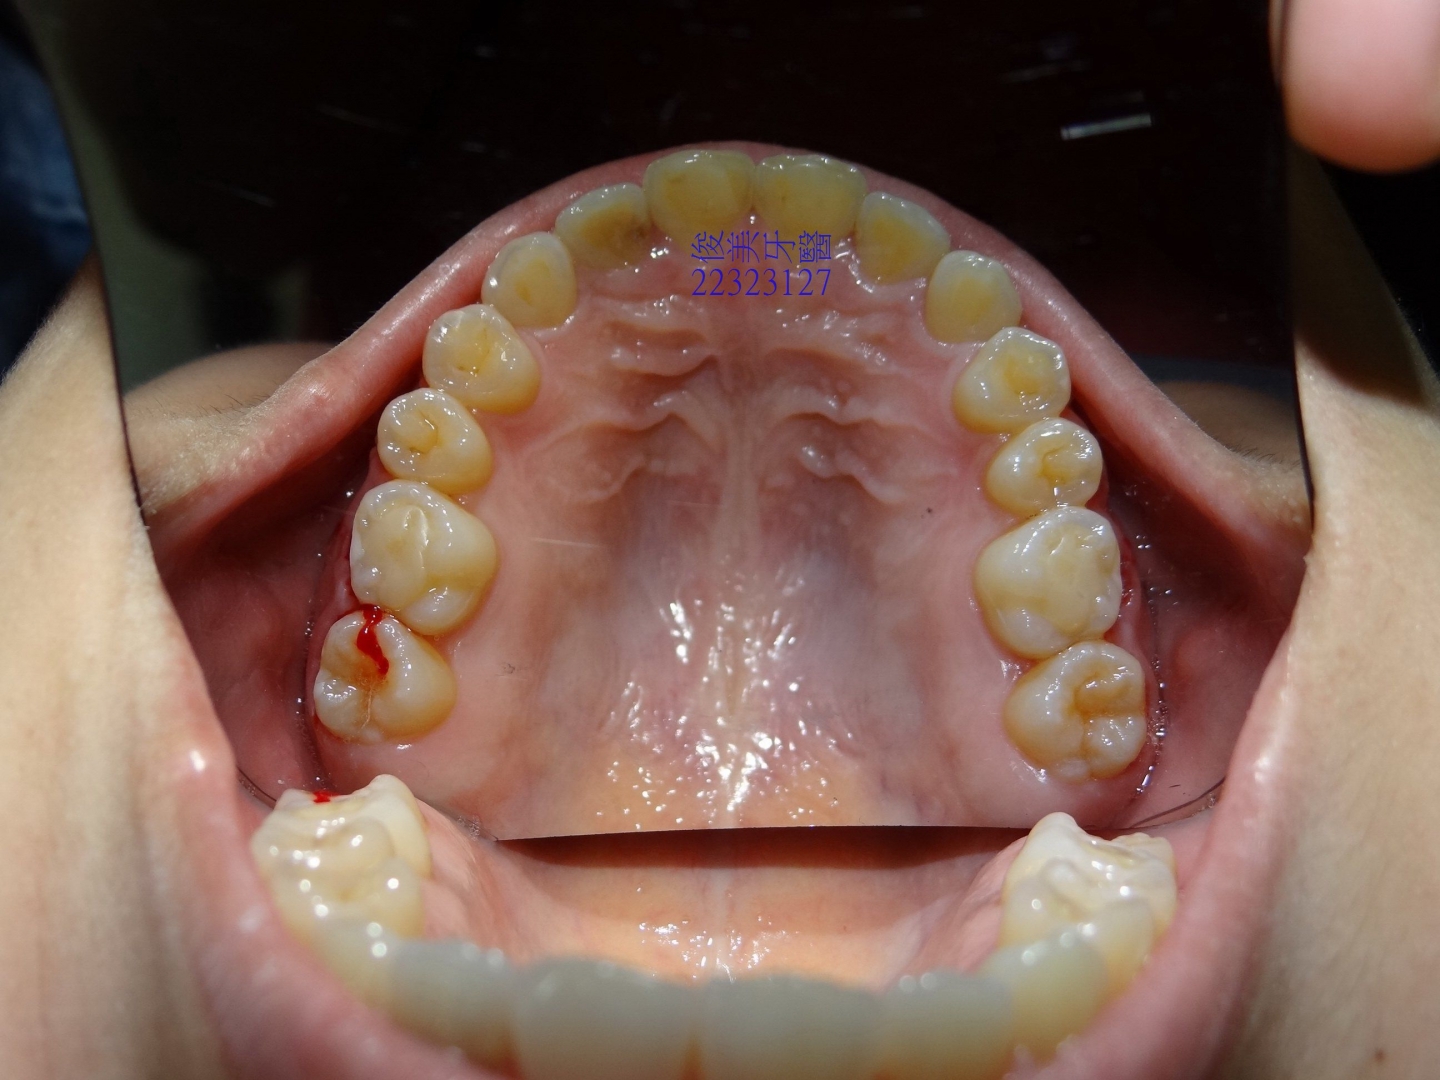

![]() 患者於門診中表示,牙齒很擁擠,想要改善;經醫師門診後,建議患者進行矯正治療即可改善。 ![]() 牙齒重疊... ![]() 有深咬現象... ![]() 上顎狀況... ![]() 下顎狀況... ![]() 左側咬合,牙齒往舌側傾斜...... . ![]() 右側咬合,牙齒往舌側傾斜...... ![]() 治療中....擁擠和深咬已改善.... ![]() 牙齒往後移.....將牙齒齒軸回正一點。 ![]() 治療結束,拆除矯正器了............. ![]() 患者好開心......牙齒整齊後,笑容更可愛了。 ![]() 也沒有暴牙的狀況。 ![]() 上顎牙弓狀況。 ![]() 下顎牙弓狀況。 ![]() 右側咬合狀況。 ![]() 左側咬合狀況。 ![]() 已拆除超過5年,依舊配戴維持器,保持最佳狀態。 |